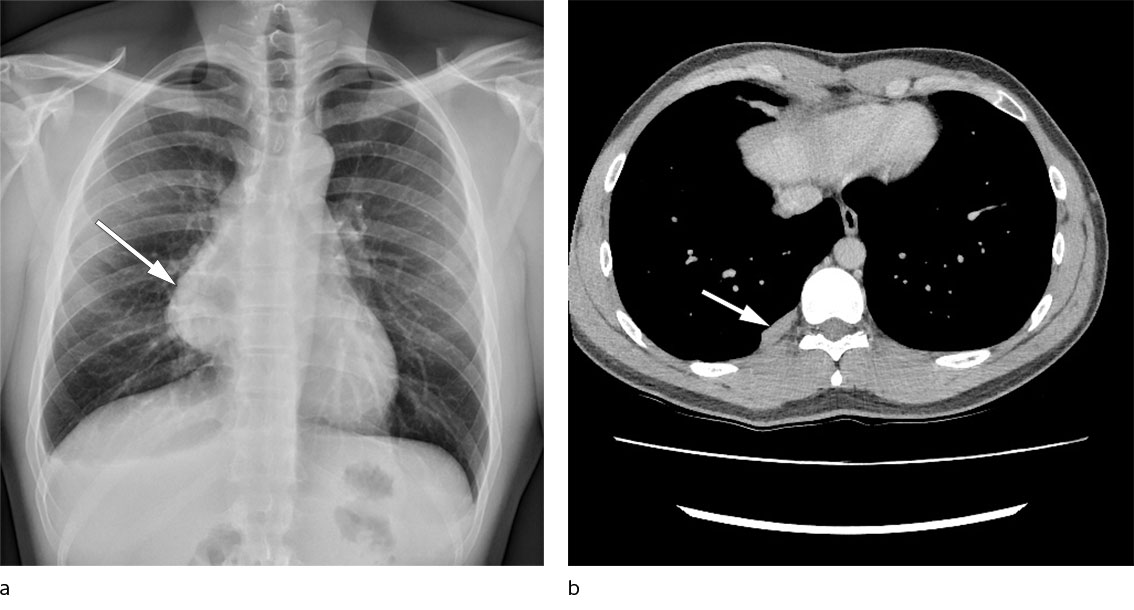

The patient, a man in his twenties, was a never-smoker with a history of childhood asthma but was otherwise previously healthy. The case history started with persistent chest pain and increasing dyspnoea on exertion following a minor trauma at the gym. Chest X-ray revealed a large new mediastinal mass on the right side compared with an X-ray taken four years previously in connection with a different trauma (Figure 1a). Chest CT revealed a tumour sized 12 × 9 × 6.5 cm in the anterior mediastinum, suspected of arising from residual thymic tissue, with no signs of invasion into mediastinal structures. A CT-guided biopsy was assessed to be type B1/B2 thymoma. The patient underwent radical surgery with sternotomy and thymectomy with no macroscopic residual tumour and no complications.

The patient received postoperative radiotherapy. He was followed up every six months with chest CT and check-ups at the respiratory medicine outpatient clinic. Two years post-surgery, three new masses were detected in the right pleura (Figure 1b). The largest was 23 mm, and on imaging it resembled the original extirpated thymoma when compared to the preoperative chest CT. The pleural masses had moderately increased uptake of FDG (fluorodeoxyglucose) on PET-CT. A CT-guided pleural biopsy found hypocellular fibrosis and striated muscle tissue.